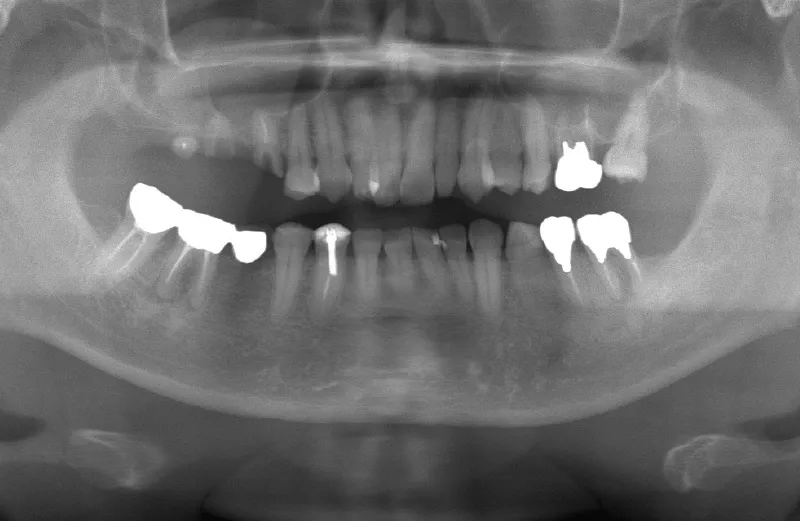

メガジェンオペの症例紹介02

治療前

治療後

| 主訴 | 左上の一番奥歯は他院にてマイクロスコープで治療してもらったが、根の状態が万全ではないのでブリッジでは治療しない方が良いと言われた。 なので左上の歯がないところにインプラントをして欲しい。 |

|---|---|

| 治療期間 | 2ヶ月で仮歯が入り、 3ヶ月で最終補綴物が入って終了。 |

| 費用 | 約550,000円 |

| 治療内容 | エクストラワイドショートインプラントを埋入し、上顎洞を移植材を用いずに挙上しインプラントを埋入した。約2ヶ月で仮歯を装着し、様々な機能面に問題がないことを確認し3ヶ月で最終補綴物を装着して終了した。 |

| 治療のリスク | インプラント埋入オペ時に術者が上顎洞内にインプラントを迷入させる可能性がある。これは術者が技術的に熟練していれば防ぐことが可能。 |